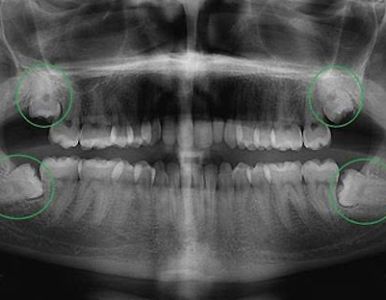

Răng khôn mọc lệch gây đau, viêm và nhiều biến chứng nguy hiểm. Tìm hiểu dấu hiệu, thời điểm cần nhổ và chi phí nhổ răng khôn tại NHA KHOA SV.

Răng khôn (răng số 8) thường mọc lệch, mọc kẹt gây đau, viêm nhiễm và nhiều biến chứng nguy hiểm. Cùng Nha Khoa SV tìm hiểu khi nào nên nhổ răng khôn an toàn.

Tìm hiểu dấu hiệu răng khôn mọc lệch, mức độ nguy hiểm và cách xử lý an toàn. Bài viết cung cấp thông tin đầy đủ, kèm video thực tế tại Nha Khoa SV.

Tìm hiểu răng số 8 (răng khôn), dấu hiệu mọc, các dạng nguy hiểm và phương pháp nhổ răng khôn chuẩn y khoa tại Nha Khoa SV.